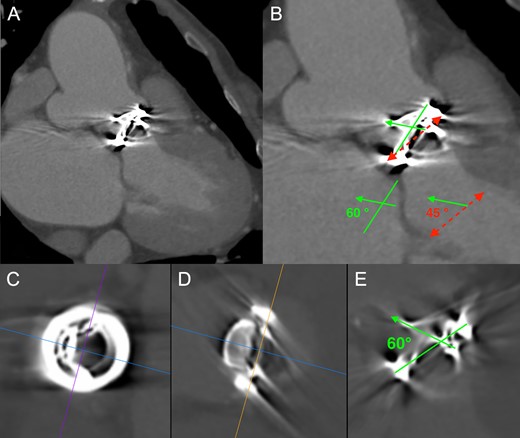

An 80-year-old woman, who had undergone aortic valve replacement with a 23-mm Björk-Shiley valve and open mitral commissurotomy at our hospital for multivalvular rheumatic heart disease at age 51, had chest tightness during exertion after many years of uneventful, asymptomatic clinical development. Follow-up transthoracic echocardiographic examinations over the past several years showed a normal left ventricular volume and ejection fraction, and moderate mitral stenosis (mitral valve area: 1.5 cm2) and an elevated peak prosthetic aortic jet velocity of 300-350 cm/s had been maintained within the boundary area without worsening. Cardiac computed tomography (CT) angiography revealed no significant obstructive coronary disease, but an unexpected saccular ascending aortic aneurysm (maximum transaortic diameter: 51 mm) arising from the posterior ascending aortic wall was observed (Fig. 1A). Transesophageal echocardiography (TEE) revealed eccentric systolic flow jets through the tilting disc valve prosthesis directly impinging on the saccular aneurysm (Fig. 2A and B, Video 1). In addition, cardiac CT angiography (systolic images) and TEE confirmed that the Björk-Shiley valve with a normal leaflet opening angle (Fig. 1C–E) was implanted with its major opening directed toward the non-coronary sinus, and was unpredictably tilted by the elevation of the prosthesis in the right-coronary sinus (Fig. 1B). The patient underwent reoperation for her ascending aortic aneurysm and possible stenosis of the prosthetic aortic valve. The ascending aorta was opened after aortic cross-clamping, and the prosthetic aortic valve and aortic aneurysm were inspected from the inside. Since the orifice of the aneurysm was located on the edge of the aortotomy suture line in the posterior wall of the ascending aorta, the lesion was probably considered a postsurgical false aneurysm. Although the Björk-Shiley valve prosthesis had no restricted leaflet motion without any obvious structural deterioration, thrombus, or abnormal pannus, it was causing an elevated transprosthetic velocity. Therefore, we decided to replace this old mechanical prosthesis with a 21-mm bovine pericardial bioprosthesis (Carpentier-Edwards Magna Ease Aortic Valve: Edwards Lifesciences, Irvine, CA, USA). The ascending aorta was replaced with a 26-mm Dacron prosthetic graft (J-Graft: Japan Lifeline Co., Ltd., Tokyo, Japan). The operative course was uneventful, and the patient recovered from surgery and has been free of complaints for almost three years.

(A) Cardiac computed tomography (CT) angiography revealed a saccular ascending aortic aneurysm (maximum transaortic diameter: 51 mm) arising from the posterior ascending aortic wall just above the sino-tubular junction. (B) Cardiac CT angiography (systolic images) confirmed that the Björk-Shiley valve was tilted by the elevation of the prosthesis in the right-coronary sinus. Red dashed line: Aortic annulus (Basal ring), Green solid line: Prosthetic valve ring, Green solid arrow: Prosthetic valve leaflet. Physiologic opening angle calculated between the leaflet of the prosthetic aortic valve and the aortic annular plane was 45 degrees. (C, D, and E) Prosthetic heart valve assessment with cardiac CT (systolic images). Short axis view (C), frontal view (D), and lateral view (E) of the Björk-Shiley spherical-disc valve in the aortic position. Multiplanar reconstruction (MPR) image analysis revealed a normal leaflet opening angle of 60 degrees.

Björk-Shiley tilting-disc heart valves, earlier-generation mechanical prostheses widely used throughout the world in the 1970–80 s, have been withdrawn from clinical use due to structural dysfunction in some models [6]. Tilting-disc aortic valve prostheses were normally inserted with their major opening directed toward the non-coronary sinus, sutured in a supra-annular position in the area corresponding to the non-coronary sinus, and slightly tilted by the elevation of the prosthesis in the non-coronary sinus for facilitating smoother systolic transvalvular flow [2, 3]. In our patient, while the 23-mm Björk-Shiley aortic valve prosthesis with a 60-degree opening angle was actually implanted with its major opening directed toward the non-coronary sinus, it was conversely tilted by the elevation of the prosthesis in the right-coronary sinus. As a result, the functional opening angle calculated between the leaflet of the prosthetic aortic valve and the aortic annular plane was 45 degrees (Fig. 1B). Corte et al. quantified the restricted cusp opening of BAV (75 ± 3° for normal tricuspid aortic valves, 76 ± 3° for non-fused cusps (non-coronary cusps), and 62 ± 5° for conjoined cusps (left-coronary and right-coronary cusps)), demonstrating that the BAV’s conjoined cusp opening angle independently predicted aortic diameter and growth rate [7]. The narrow functional opening angle of the tilting disc valve prosthesis might have affected not only the elevated peak prosthetic aortic jet velocity but also the development of ascending aortic aneurysm in our case.